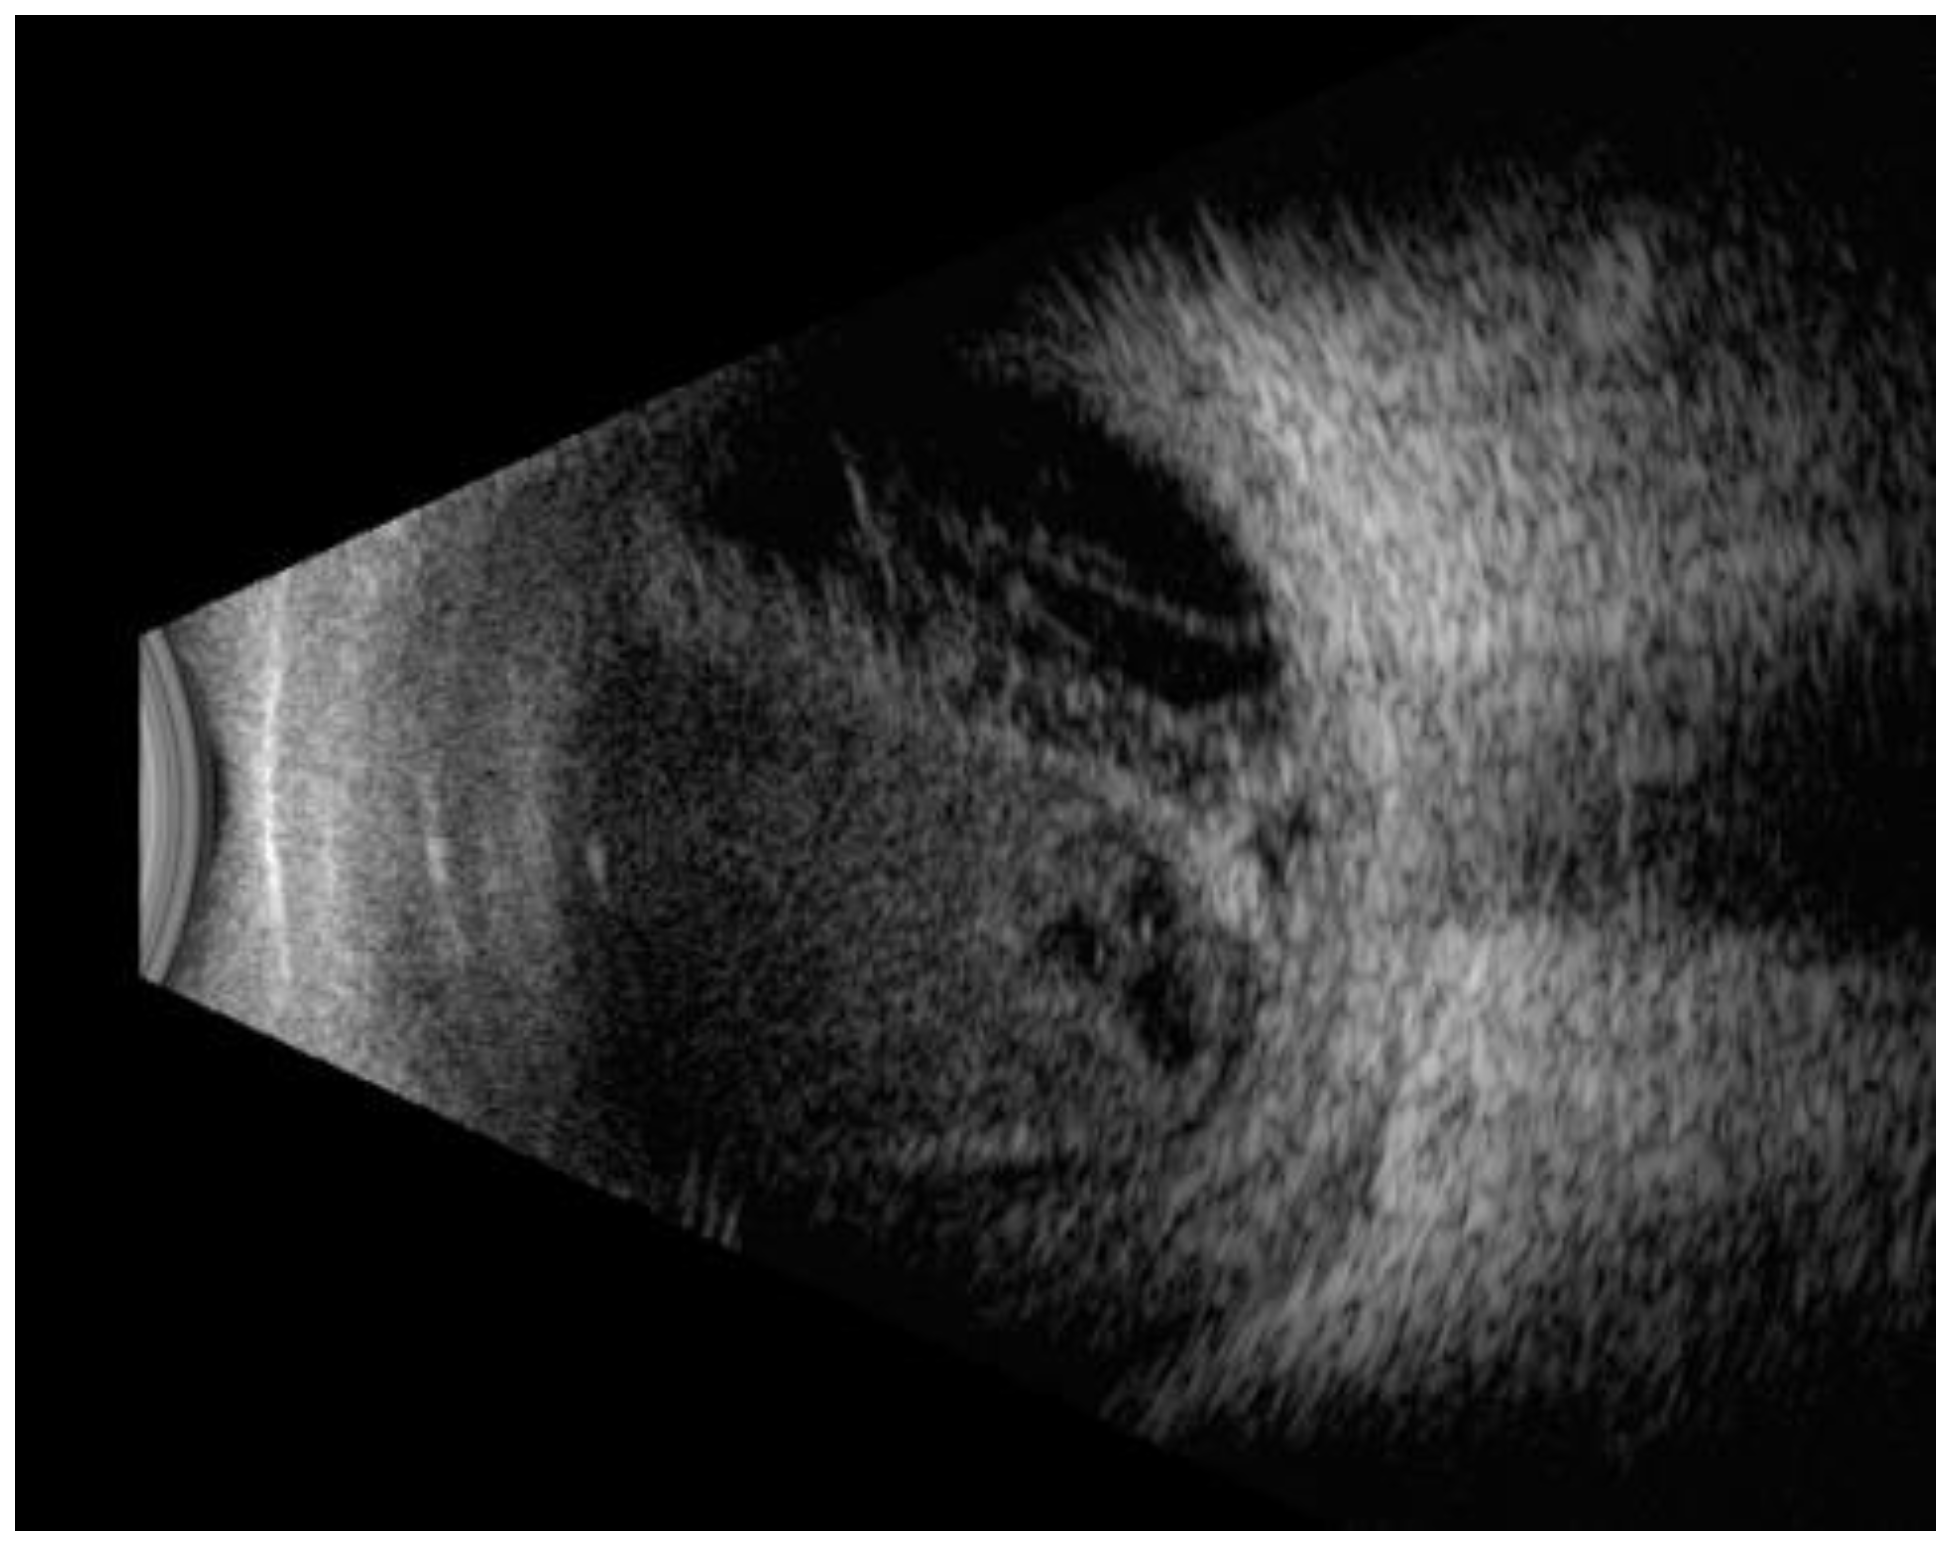

Ocular ultrasound exam (B-mode)

| 53 (94.6%) 12 (21.4%) 3 (5.3%) | 23 (95.8%) 4 (16.6%) 1 (4.1%) | 30 (93.7%) 8 (25%) 2 (6.25%) | 0.08 |